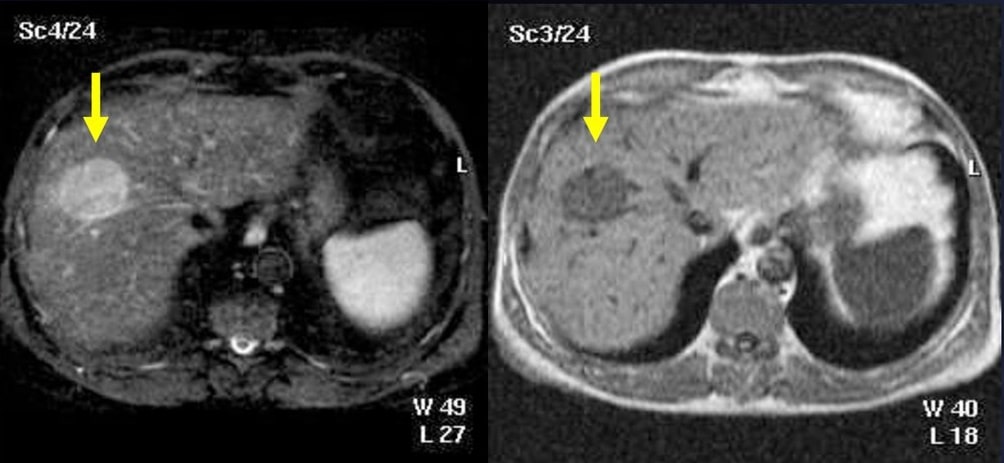

Методы динамического контрастирования печени на МРТ

Раздел: Снимки-подсказки